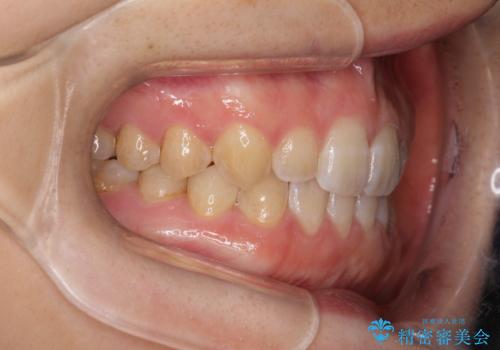

前歯の隙間を閉じたい インビザラインによる矯正

- 上下の前歯に隙間があるとのことで来院されました。

インビザラインにて隙間を閉じる矯正を行いました。

使用時間を守っていただけたので、比較的スムーズに矯正を終了することができました。